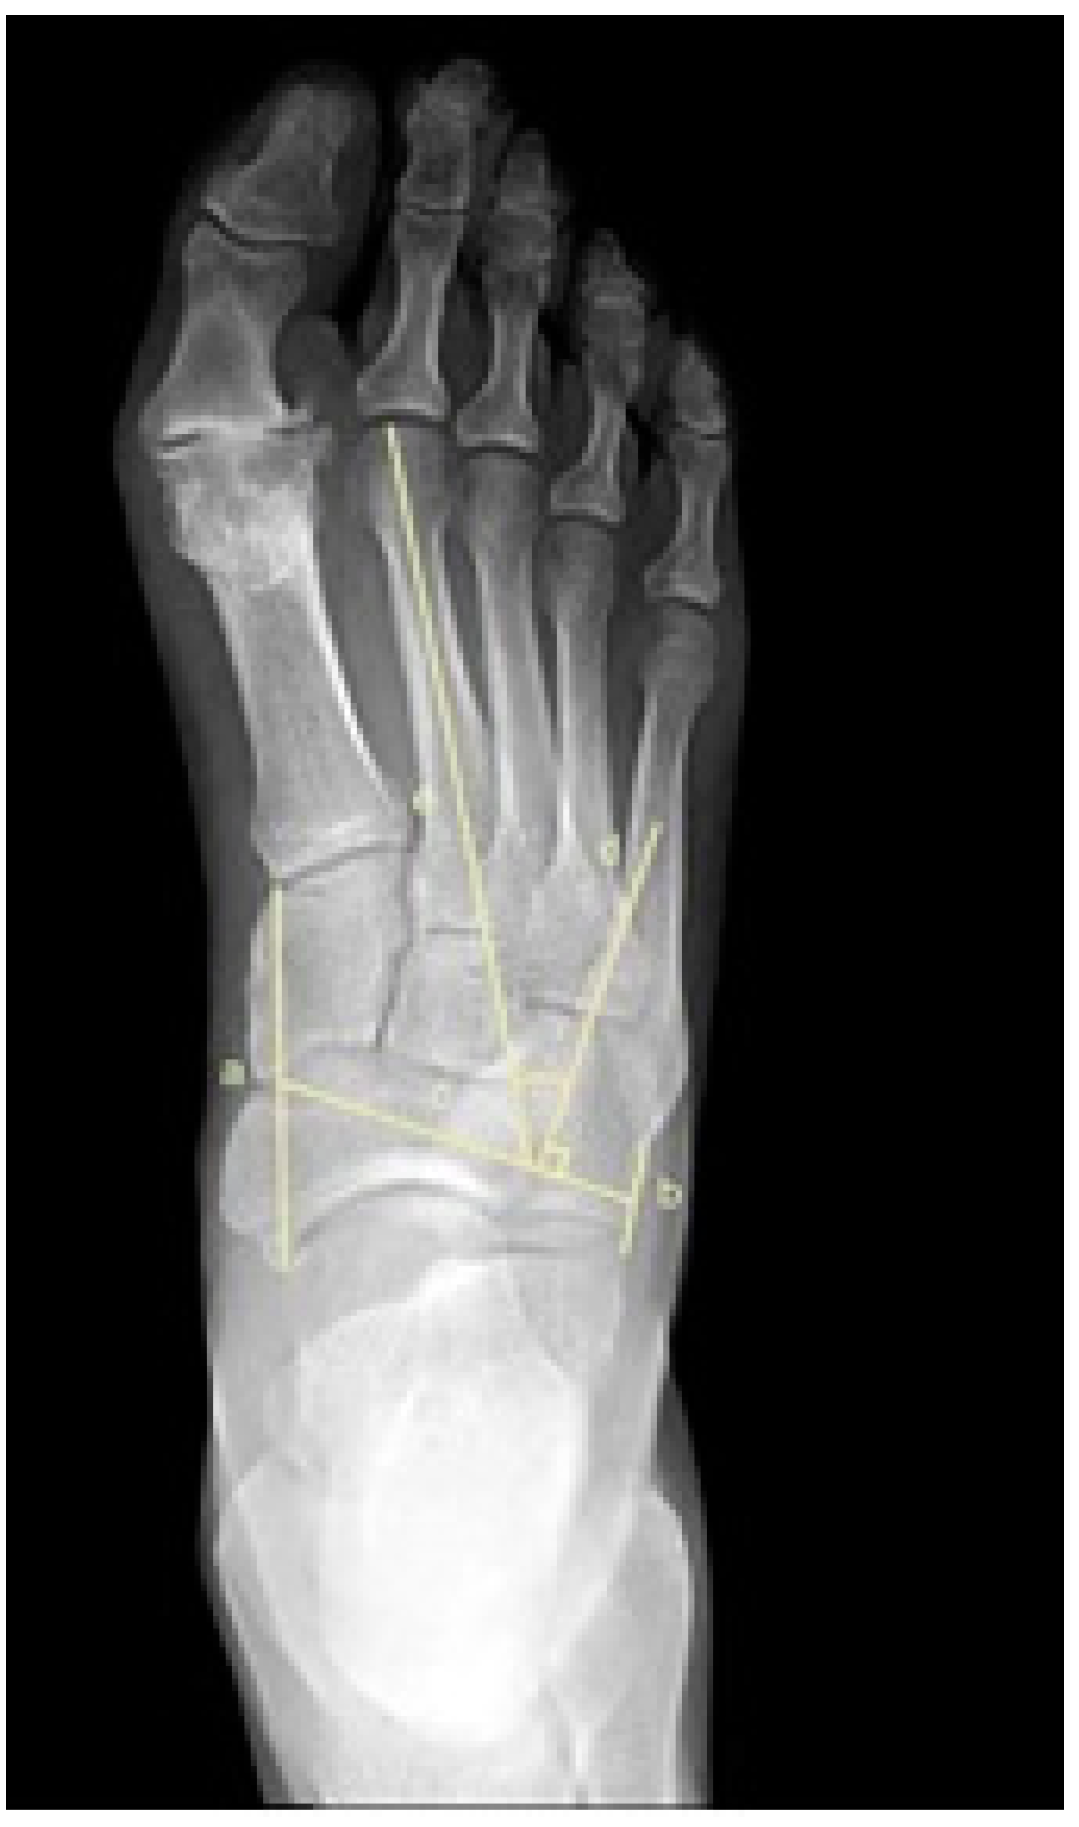

2.5. Metatarsus Adductus Measurements

- Engel, E.; Erlick, N.; Krems, I. A simplified metatarsus adductus angle. J. Am. Podiatry Assoc. 1983, 73, 620–628. [Google Scholar]